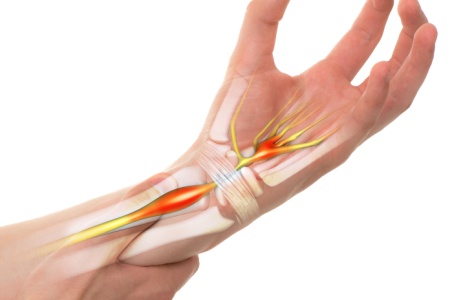

Numbness and tingling are sensations that occur when nerves are irritated, compressed, or damaged, often described as pins and needles. Causes can include nerve compression from spinal misalignment, herniated discs, poor circulation, or conditions such as diabetes. Risk factors include repetitive strain, sedentary habits, injuries, and underlying health issues. Symptoms may appear in the hands, arms, legs, or feet and can interfere with daily activities. A chiropractor can provide relief by identifying the source of nerve irritation, performing gentle adjustments to improve alignment, and recommending posture and lifestyle changes to reduce strain. If you are experiencing persistent numbness and tingling, it is suggested that you consult a chiropractor who can guide you toward natural, effective treatment solutions.

Numbness and tingling sensations can disrupt daily life, often arising from issues like nerve compression, poor circulation, or structural imbalances. These symptoms, commonly felt in the hands, feet, arms, or legs, range from mild pins and needles to persistent discomfort. Conditions such as herniated discs, carpal tunnel syndrome, or peripheral neuropathy are frequent causes, often linked to irritated or restricted nerve pathways. Left untreated, these sensations may worsen, leading to reduced mobility or further nerve damage.

Chiropractic care addresses numbness and tingling by focusing on the root causes. A chiropractor evaluates spinal alignment, nerve function, and contributing factors like posture or muscle tension. Through targeted adjustments and therapies, they relieve nerve compression, improve circulation, and restore function. Lifestyle recommendations complement treatment, offering long-term relief and promoting nerve health.

Not always. While often linked to nerve compression, these sensations can also result from poor circulation or systemic conditions. Chiropractors assess for nerve involvement and recommend appropriate care or referrals.